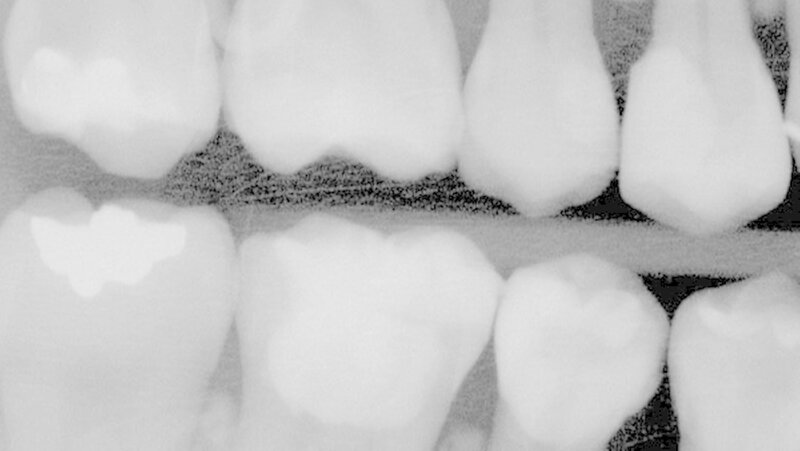

Das Röntgenbild zeigte, dass die Füllungen bei Zahn 45 und 46 nahe an der Pulpakammer lagen. Mit EPT (32/80, 35/80) und thermischen Tests wurde die Pulpavitalität geprüft (normal). Die Diagnose lautete: tiefe Karies. Die Kompositfüllungen wurden daraufhin möglichst substanzschonend ersetzt.